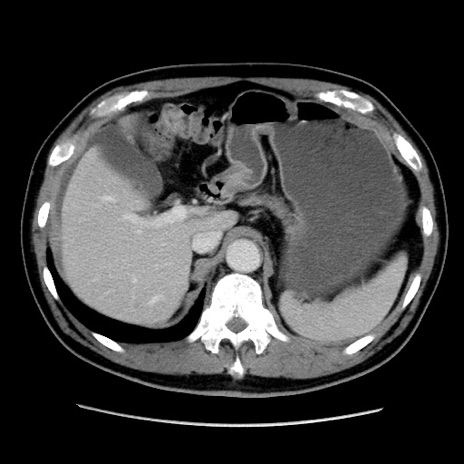

症例16(横断像)

【症例】 70歳代男性

【主訴】 腹痛、嘔吐

【現病歴】 約1ヶ月前より間欠的に腹痛と嘔吐あり、当院消化器内科を受診したところCTで多発する肝臓のLDAを指摘され、精査中であった。以降は消化器症状は安定していたが、2日前より嘔気と腹痛があり、同日より排便・排ガスが消失した。改善認めず、 本日、救急外来を受診した。

【既往歴】 大腸ポリープ切除後。

【身体所見】意識清明・会話良好、BT 36.3℃、BP 127/80mmHg、 P 80bpm、腹部:膨満あり、平坦・軟、上腹部正中および下腹部正中に圧痛あり、反跳痛なし、筋性防御なし。

【データ】WBC 7200、CRP 0.77